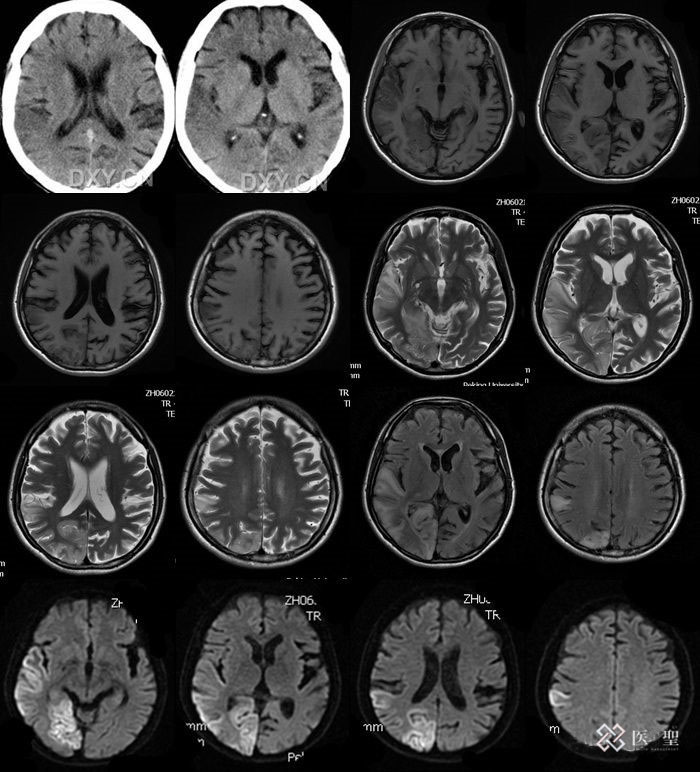

头颅mr影像

脑精密检查:头部MRI・MRA、颈部MRA,可发现造成蛛网膜下腔出血原因的动脉瘤,检查是否有较小的脑梗塞病灶,通过磁场产生图像,人体不会受到放射线的辐射。颈动脉超声波检查,可以发现动脉硬化的进展及管壁的肥厚和狭窄的情况。